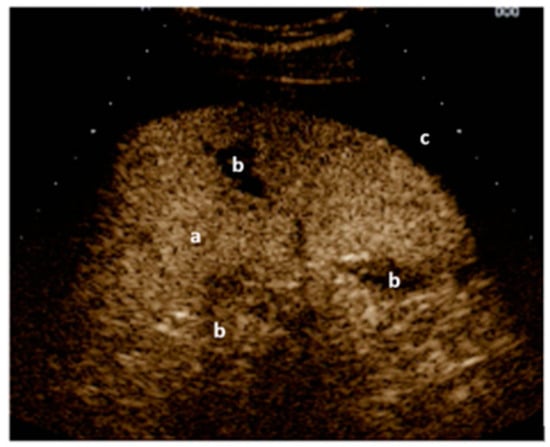

Figure 2.

Left upper quadrant view: CEUS of the spleen (a) with black gaps (b) within the spleen (lacerations/ruptures) and around the spleen (free fluid/blood) (c). Image courtesy of J. Osterwalder.